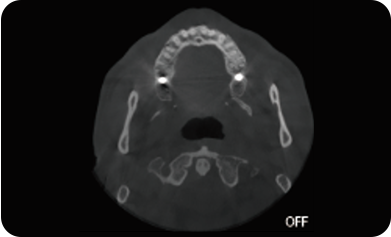

超能去伪 至臻影像

局部超清显示、 移动视野摄片

真人正侧位投影,实现CT成像区域无极可调

可根据临床需求任意调整成像区域大小实现局部超清三维显示

可根据临床需求任意调整成像区域大小实现局部超清三维显示

临床样片